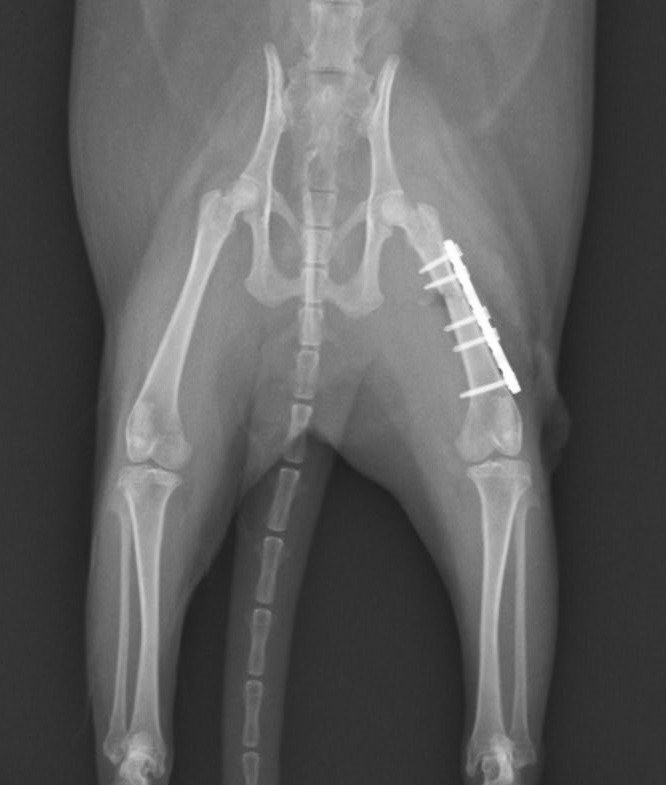

大腿骨骨折のフェレットちゃんの手術依頼でご紹介がありました。TAITAN1.2プレートを使用し無事歩けるようになりました。よかったね。